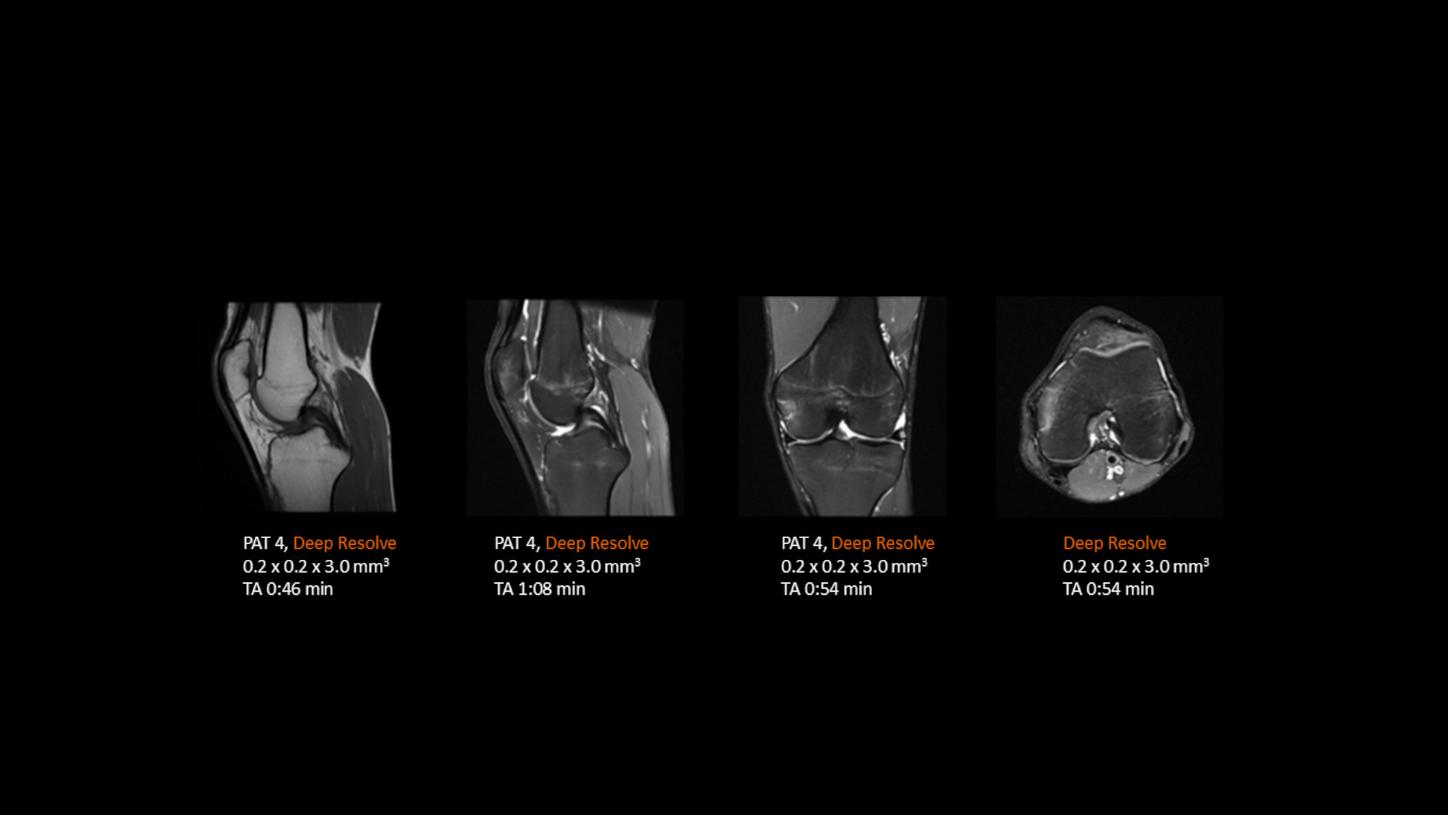

Deep Resolve is at the forefront of the revolution in MRI acceleration. Deep Resolve delivers our fastest MRI, delivering images of extraordinary clarity, higher clinical productivity, and a better patient experience.